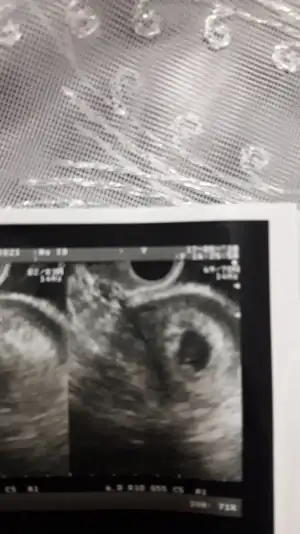

Bu da kurtaj oldugum gebelik

Kizlar orda bebegi goruyorum sanki siz goruyor musunuz?